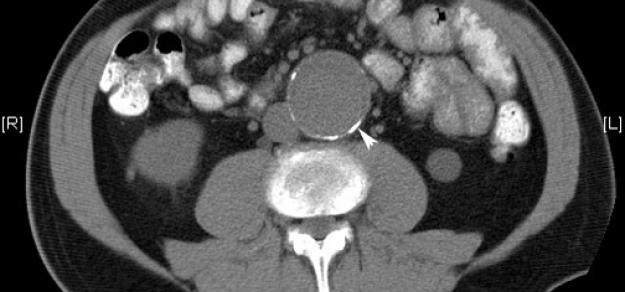

Heart, 1 de abril de 2019 la prescripción de metformina podría limitar la expansión de la AAA entre los pacientes con esta enfermedad, y podría estar involucrada con una menor incidencia de aneurisma aórtico y eventos de aneurisma aórtico